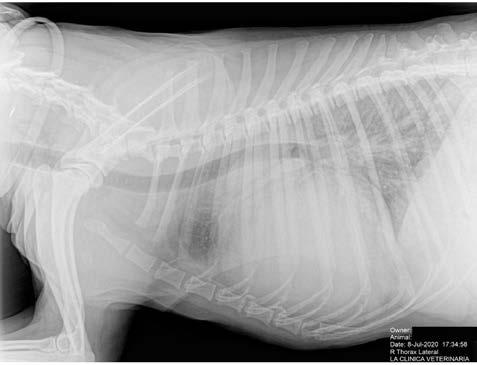

Se realiza radiografía de tórax (Fig. 1) que revela car-

diomegalia generalizada severa, índice de Buchanan de 15 cuerpos vertebrales, que puede corresponder a un severo aumento de las cámaras cardiacas, o a la presencia de líquido pericárdico. Se observa, además, un patrón pulmonar intersticial perihiliar, compatible con edema pulmonar, foco de neumonía o hemorragia pulmonar.

M. López,1 V. Fernández,2 J. Engel3 1Servicio de cardiología y diagnóstico por imagen. 2Servicio de cirugía. Laclinicaveterinaria. c/Marroquina 26. 28030 Madrid. 3Servicio de cardiología. ANICURA-Benipeixcar Hospital Veterinario. Avinguda de la Constitució 68, bajo izq. 46009 Valencia. ANICURA-San Francisco Hospital Veterinario. c/ Sant Francesc 65. 12500 Vinaròs (Castelló). ANICURA-San Vicente Hospital Veterinario. c/ Veterinario Manuel Isidro Rodríguez García 17. 03690 San Vicente del Raspeig (Alicante). Figura 1. Radiografía lateral de tórax en la que se observa cardiomegalia generalizada, VHS 15. Patrón alveolar intersticial compatible con edema pulmonar. Patrón vascular mixto y patrón bronquial en lóbulos caudales, compatible con bronquitis crónica, mineralización por degeneración senil.

En el caso que presentamos podemos confirmar cardiomegalia severa y edema pulmonar dado que el estudio radiológico del tórax permite establecer el tamaño cardiaco y valorar el patrón pulmonar. La insuficiencia cardíaca congestiva izquierda se caracteriza por un patrón intersticial, que puede evolucionar a patrón alveolar en la región perihiliar que tiende a distribuirse hacia caudodorsal, característico del edema pulmonar cardiogénico, patrón vascular venoso.